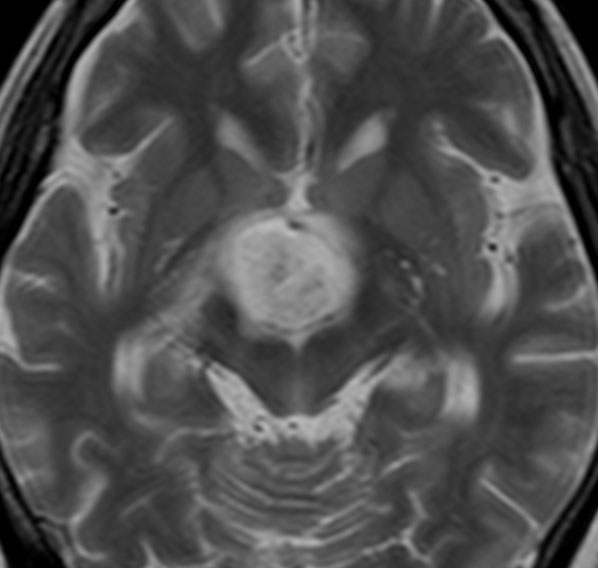

4歳で,第3脳室内のクラニオを2度の開頭手術で摘出され,

6歳の時にガンマナイフ治療を受け,下垂体機能は部分的に温存されて成人になりました

このMRIは25歳の時のもので,経過を見たら前頭葉内のう胞もできて増大してきました

しかたがないので開頭手術で摘出しました